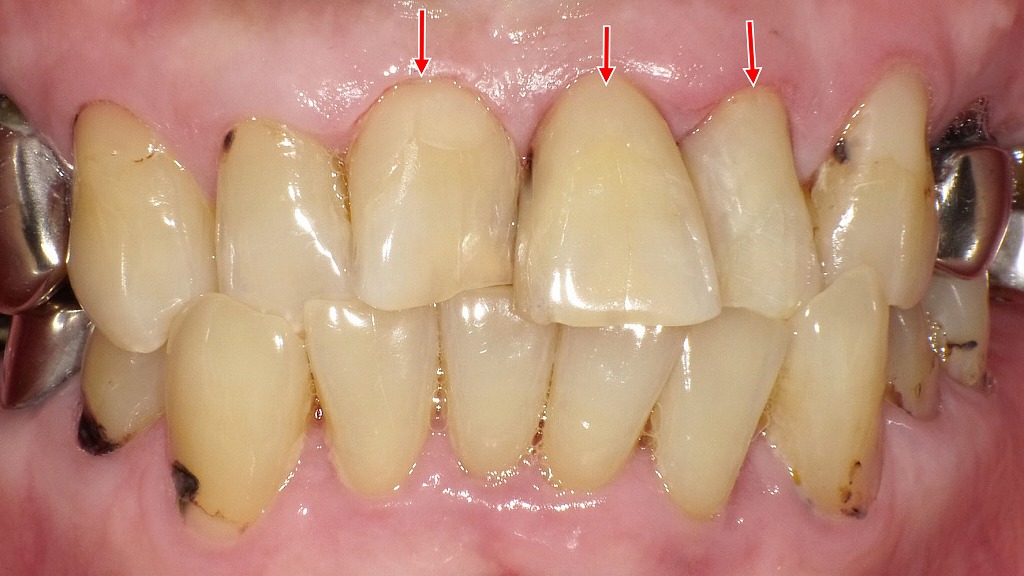

経年劣化・着色・境界部分が変色した症例

コンポジットレジンは見た目が自然で使いやすい材料ですが、経年変化によって 着色・変色・表面の摩耗・欠け(チッピング) が起こりやすい傾向があります。写真では、修復部の微小な欠け、段差の形成、境界部分の変色が認められ、レジン特有の劣化が進行した状態が確認できます。また、噛む力が強くかかる部位では破折や脱離が起こることもあり、定期的なメンテナンスや再修復が必要になる場合があります。